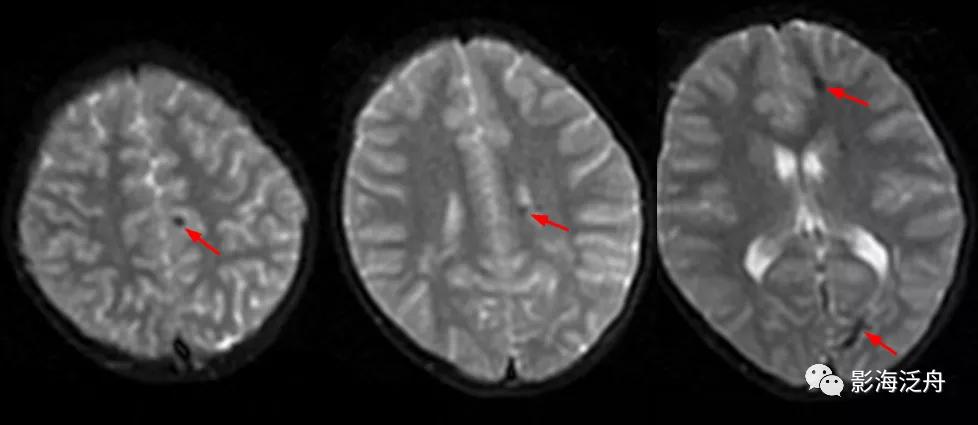

SWI可见左侧大脑半球多发低信号结节(红箭),病灶多位于皮髓质交界区,直径较为一致,结合患者年龄、病史,不难诊断这是一例多发海绵状血管瘤。

诊断虽然明确了,但故事到这里还没结束,回过头去看患者第一次检查的低b值DWI序列,可以发现这些病灶其实早就存在。但为什么第一次检查的时候没有及时发现呢?想必这大概率是因为大家对低b值DWI序列认识不足造成的,尤其是低年资诊断医生和神经科临床医生往往会自动忽略掉低b值DWI序列,再或者就是把低b值DWI误认为是高b值DWI序列。

在低b值DWI序列可以看到左侧大脑半球多发磁敏感伪影(红箭)。